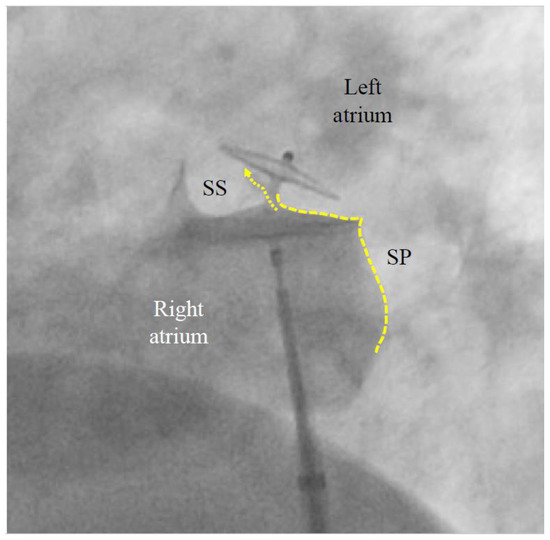

A contrast medium injection is carried out after flushing the sheath and after adjusting the projection so that both discs are seen in perfect profile without any overlap. It will show all necessary details (Figure 3). The device is then released, i.e., unscrewed from the pusher cable or liberated by whatever attachment and release mechanism is used with alternative occluders. A further contrast medium injection after readjusting the projection is required only if the device moves significantly upon release. This typically happens in the presence of an atrial septal aneurysm (ASA) or due to significant position distortion by the sheath or pusher gear before release (Figure 3).

Figure 3.

Contrast medium injection before release of a patent foramen ovale (PFO) occluder (left anterior oblique view). The left (cranial) part of the 25/18 mm Amplatzer PFO Occluder correctly bites into the septum secundum (SS). This is called a positive Pacman sign and is required for safe release. The original channel of the PFO is now blocked (dotted arrow). The septum primum (SP) is indicated with a dotted line. Its part caudal to the occluder is ideal for possibly later required fluoroscopy-guided transseptal punctures. A pre-release situation like this will usually have the device swivel up to a clockwise quarter turn upon release. The final occluder position is expected to be more vertical and parallel to the atrial septum with no more dent in the SP.

PFO closure will not render more intricate subsequent left atrial access for catheter-based interventions such as ablation for AF, LAA closure, or mitral valve interventions. On the contrary, a visible PFO occluder delineates, just caudal to it, a safe area for fluoroscopically guided transseptal puncture of the septum primum (Figure 3) [60].